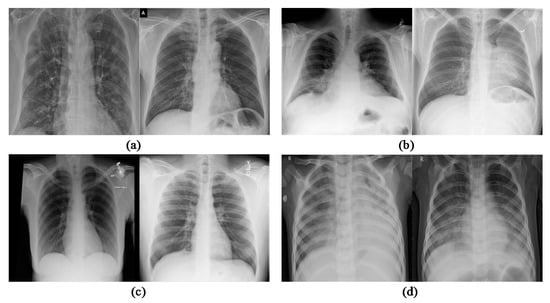

2.1. Dataset for Experiment

- Step 3: ClassificationAll the features are extracted using Inception V4 from Chest XR images and then the multiclass SVM (MSVM) classifier is applied. The classification with the proposed C19D-Net model classifies the Chest XR images into multi-classes as “normal”, “viral pneumonia”, “COVID-19” and “bacterial pneumonia” with high precision as associated with other models or methods as discussed below in coming sections.